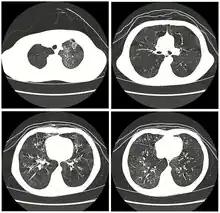

| High resolution CT scan showing bronchiolitis obliterans with mosaic attenuation, bronchiectasis, air trapping and bronchial thickening[3] | |

Early in the disease chest radiography is typically normal but may show hyperinflation.[6] As the disease progresses a reticular pattern with thickening of airway walls may be present.[4][6] HRCT can also show air trapping when the person being scanned breathes out completely; it can also show thickening in the airway and haziness in the lungs.[11] A common finding on HRCT is patchy areas of decreased lung density, signifying reduced vascular caliber and air trapping. This pattern is often described as a "mosaic pattern", and may indicate bronchiolitis obliterans.[6]